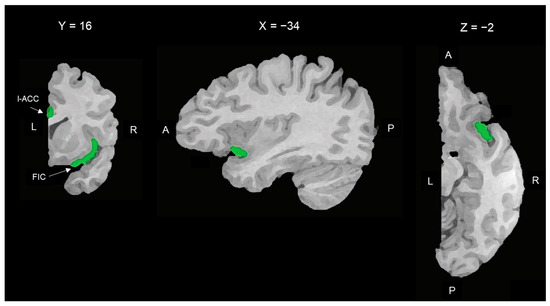

Two-dimensional maps of the subnetworks resulting from the voxel-wise parceling of the ROI-generated functional network (fuzzy clustering) of the whole sample (HCs + SZ). HCs: healthy controls; SZ: patients with schizophrenia. Connectivity-based parceling of the VEN-derived functional network. Each panel represents a probabilistic map of one of the four functional connectivity-defined subclusters. These subclusters were associated with four well-known functional networks: the salience network (A), the superior frontal network (B), the orbitofrontal network (C), and the central executive network (D). L = left; R = right; A = anterior; P = posterior.

From the between-group (HC vs. SZ) comparison, statistically significant differences were found within the salience network (SN) cluster only. The SZ group showed lower connectivity of the SN in terms of the extension and intensity of the functional cluster. In particular, compared to HCs, patients with SZ showed lower connectivity values in four subclusters within the SN cluster corresponding to the right anterior insula (R-AI), the bilateral dorsal ACC (d-ACC)/pre-supplementary motor areas (pre-SMA), the right ventral striatum (R-vSr), and the right ventral tegmental area (R-VTA; Figure 4).

Figure 4.

Between-group comparison of rsFC within the salience subnetwork. Two-dimensional representation of the subcluster belonging to the salience network derived from the fuzzy clustering analysis of the VEN-derived functional connectivity network. HC: maps of healthy controls; SZ: maps of patients with schizophrenia; HC > SZ: maps of the HC versus SZ between-group contrast. The areas shown in the HC > SZ maps indicate higher connectivity of the salience network in terms of the extension and intensity of the functional cluster in the HC group compared to the SZ group. These areas correspond to the right anterior insula, the bilateral dorsal ACC/pre-supplementary motor areas, the right ventral striatum, and the right ventral tegmental area (R-VTA). Corrections for multiple comparisons performed at the cluster level using 1.000 Monte Carlo simulations (p < 0.05), leading to a cluster threshold of K > 22 voxels in the native resolution.